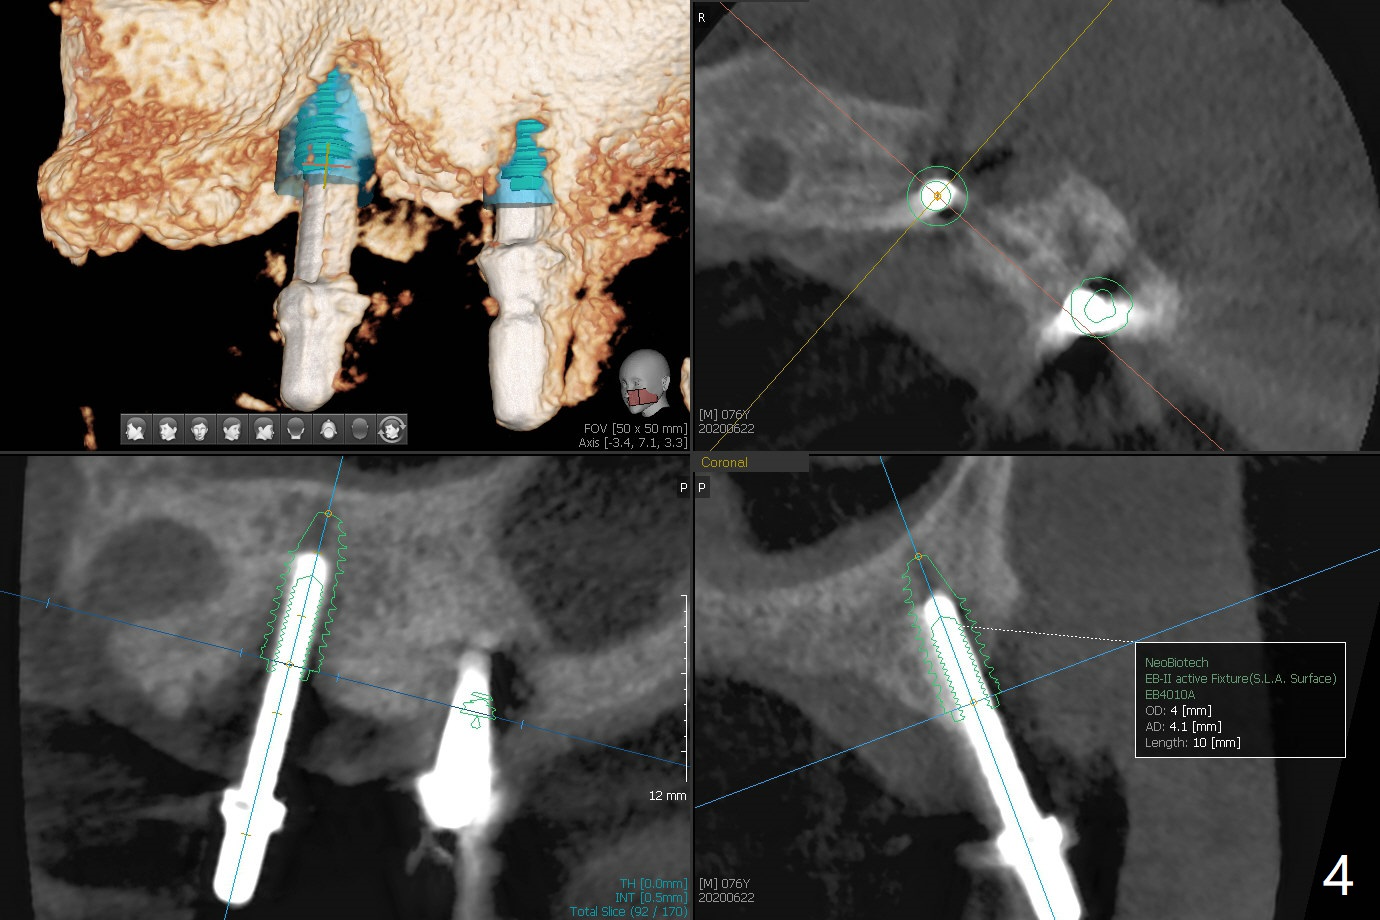

Osteotomy at #13 starts blindly (no incision or tissue punch) with bone expanders. After insertion of parallel pins, intraop CT shows that it is palatal with apparently buccal low bone density (Fig.1); the osteotomy for implant (Fig.2 green) should be shifted buccal and tilted mesial (red, parallel to #11) with incision. In contrast the position, trajectory and depth (Fig.3 <) of the initial osteotomy are acceptable at #11. The implant will be placed as it is (Fig.4). After taking a postop PA (Fig.5), the implant at #11 is placed a little deeper to make sure its slightly subcrestal placement (including distal incision at #11). Following placement of 3.5x4 and 3 mm ball abutments at #11 and 13, cortical allograft with PRF is placed around the implants, especially buccal (Fig.6,7 <). After suturing, the profile of the ball abutments is too low for RPD retention. Due to gravity other than bone density, the number of ball abutments for the maxilla should be more than for the mandible. Soft reline is done to the patient's satisfaction. The retention of the upper RPD after soft reline is satisfactory without pain 7 days postop (Fig.8). The implant at #13 is loose nearly 3 months postop (Fig.9 *: bone loss). The implant is removed while the ball abutment is untightened; the sinus floor is present. It appears that a longer and larger implant is necessary; a 4.5x10 mm dummy implant is unable to be seated deep or achieve primary stability (Fig.10). After sinus lift with 3 mm Bicon osteotome without bone graft, the dummy implant accomplishes the 2 tasks mentioned above (Fig.11). However there is no corresponding definitive implant in stock. Implant system needs to be changed; with a change in implant driver, the depth control is lost. The final implant is placed deep (Fig.12). With back up, stability is lessened; a healing screw is placed; with collagen plug, the wound is sutured (Fig.13). The wound heals 1 week postop (Fig.15). The RPD is soft relined. Retention from the ball abutment at #11 is apparently critical. The RPD and #11 implants (4 months postop) are stable, while the wound at #13 heals 1.5 months postop (Fig.15). There is space around the implant 5.5 months postop (Fig.16 *). The 5x10mm SM implant is found to be loose upon uncover and removed. After debridement, 5.3x8 mm SM and 5.5x9 mm IBS dummy implants are inserted without stability, while 6x9 mm definitive one with stability (Fig.17). Cortical allograft is placed in deficiency areas (*). The osteotomy has no roof (sinus floor), but the sinus membrane is intact. Small amount of bone graft (Fig.18 *) is placed before implantation. There appears to be bone around the new implant (Fig.19 (3D sagittal section) *).